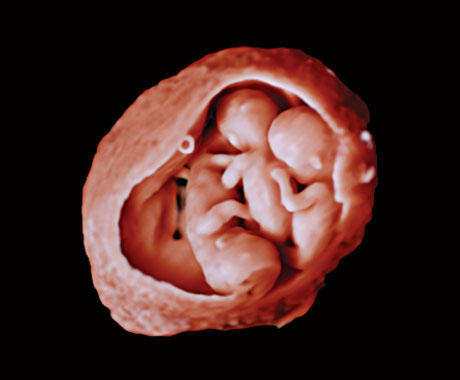

En este vídeo, el Dr. Michael Ruma presenta el transductor V9-2 para ultrasonidos 3D de Philips. El V9-2 es el primer transductor mecánico PureWave para ultrasonidos 3D de la división de ultrasonidos de Philips específico para obstetricia/ginecología y ofrece una extraordinaria calidad de imagen y un diseño ergonómico avanzado. El V9-2 está especialmente indicado para la adquisición de imágenes 2D, 3D y 4D para exploraciones obstétricas del primer, segundo y tercer trimestre..

Combinar el nuevo transductor V9-2 con el sistema de ultrasonidos de alta gama EPIQ Elite ofrece una adquisición de imágenes superior de obstetricia/ginecología: